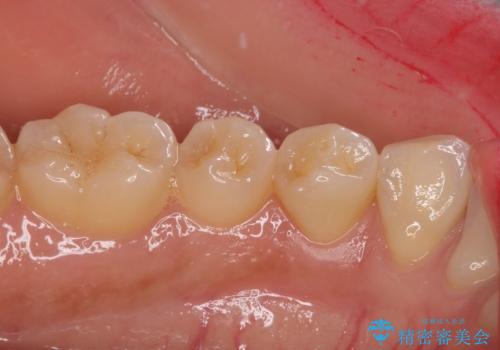

痛みでうずく 根管治療と補綴治療

- 下顎の小臼歯が食事などの度に痛みを感じるとのことで来院された患者様です。

レントゲン写真などで診査を行ったところ、左下の第一小臼歯の神経組織が壊死し、根尖部周辺の骨に炎症が認められました。

まずは根管治療を行い、症状が消退したことを確認してオールセラミッククラウンにて補綴治療を行うこととしました。

根管治療後6ヶ月でレントゲン写真を撮影したところ、根尖部周辺の炎症が消退していることが認められました。